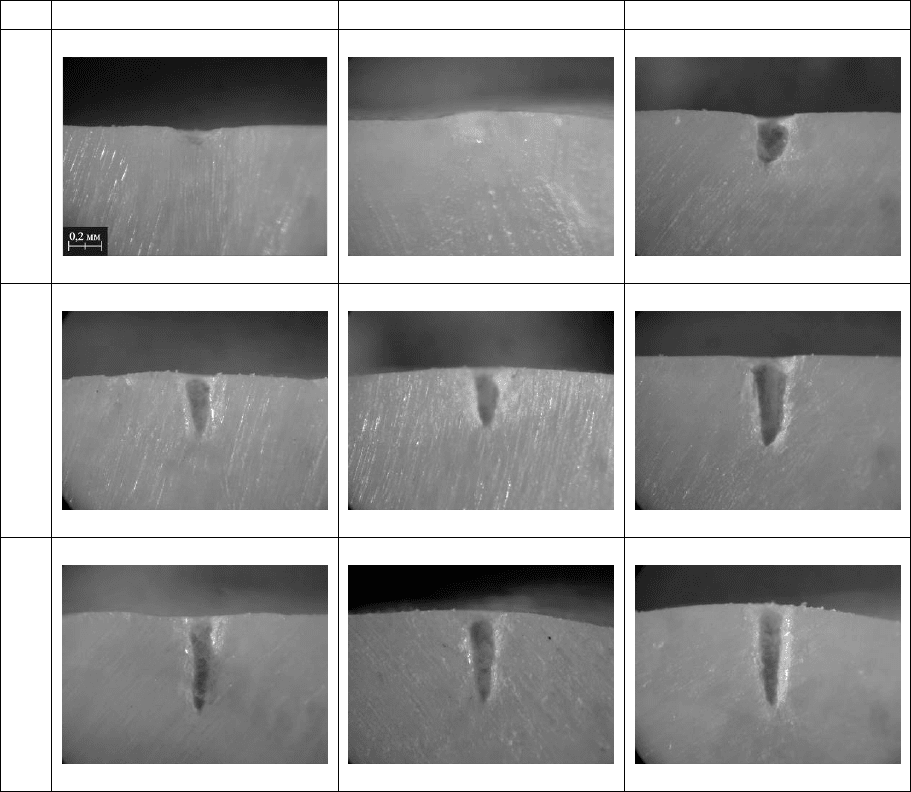

На рис. 7.5 представлены зависимости эффективности удаления эмали

и дентина зуба человека излучением импульсов YSGG: Cr, Er лазера

различной длительности и структуры от количества этих импульсов,

падающих в одну точку поверхности твёрдой зубной ткани.

Видно, что при однократном лазерном воздействии наибольшая

эффективность удаления эмали и дентина реализуется для импульса с

длительностью 1,8±0,2 мс, состоящего

из эквидистантой последовательности

пичков длительностью порядка 500 нс (тип III). Далее следует импульс

свободной генерации длительностью 1,8±0,2 мс, состоящий их хаотически

расположенных во времени пичков длительностью порядка 1 мкс (тип II).

Минимальная же эффективность удаления эмали и дентина соответствует

импульсу свободной генерации длительностью 550±50 мкс, который состоит

их хаотически расположенных во времени пичков длительностью порядка

1 мкс (тип I).